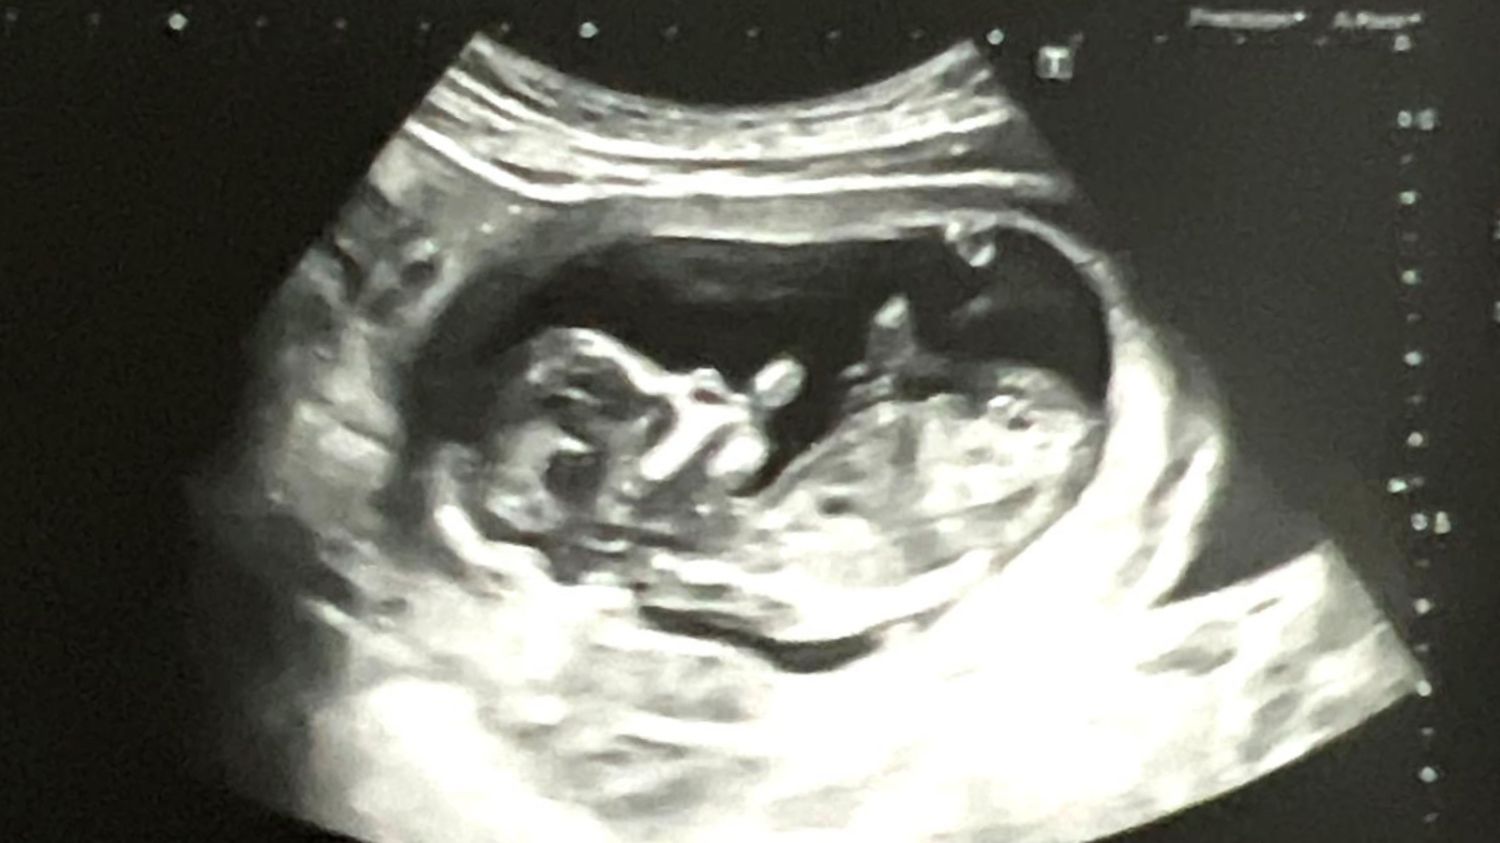

El Día del Niño por Nacer se conmemora el 25 de marzo de cada año, una fecha que hace más de tres décadas se celebra en el país, con el objetivo de defender la vida humana del embrión en el vientre materno. La jornada hace referencia a uno de los acontecimientos que recuerda la Iglesia Católica acerca de la Virgen María y la llegada de Jesús.